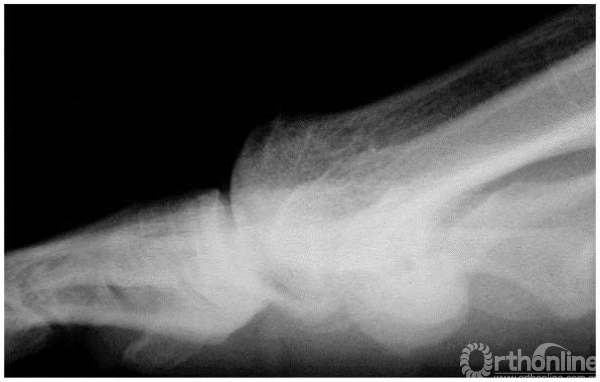

3期:正位X线上,关节间隙广泛变窄,籽骨形态不规则

3期:侧位X线上,关节间隙变窄,累及超过1/4的关节间隙,背侧骨赘更为明显

4期:关节炎表现较3期更为明显、严重(3,4期影像学表现可以差别不大,但临床表现却相差很大)